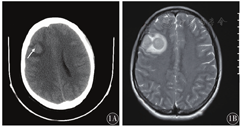

入院查体示:神志清楚,精神差,急性面容,双侧瞳孔等大等圆,对光反射灵敏,双眼视力下降,伸舌居中,口齿清楚,心肺听诊无异常,腹软,全腹未触及压痛、反跳痛,四肢肌力肌张力正常。入院血常规:WBC 5.6×109/L,中性粒细胞3.8×109/L,血红蛋白(Hb)116 g/L,血小板计数(Plt)350×109/L;凝血酶谱、生化、免疫系列、肿瘤标志物等检查均未见明显异常。头部CT示:右额叶占位,右侧脑室稍受压(图1A)。头颅磁共振平扫+增强示:右侧额颞叶多发结节,淋巴瘤?(图1B)。2018年7月26日行B型超声引导下右额占位病变活组织检查,快速冷冻可见大量幼稚细胞(图2),免疫组织化学示:CD34阳性(图3A)、CD43阳性(图3B)、CD117阳性(图3C)、MPO阳性(图3D)、CD68阴性。2018年7月27日脑脊液检查:乳酸脱氢酶274 U/L,幼稚细胞0.80,WBC 1.280×109/L,嗜碱细胞0.08。查脑脊液BCR-ABL基因阳性。确诊为CML中枢神经系统急变期。患者诊治过程中,病情持续加重、恶化,未行骨髓评估,后自动出院,电话随访死亡。